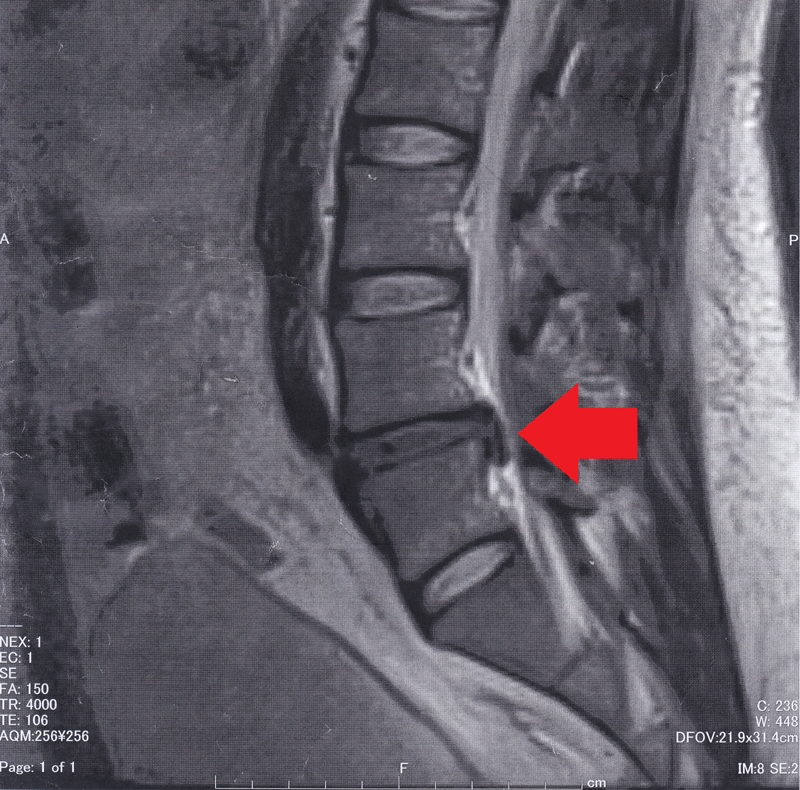

病院に到着してから2時間ほど放置されて、MRIを撮りました。

赤い矢印で示した黒い線の部分を突き破り白い神経を押している半透明の拡がってる物が髄核の一部だそうです。

かなり飛び出してるようで、医師も驚いてました。ただ、見舞いに来た弟だけは大笑い…「あ~~~はははははぁ、マジでめっちゃ飛び出てるなwwwwwwww」と、手をバンバン叩いての笑いよう。弟は看護師で、MRIとかも結構見ているみたいで分かるらしいのですが、それにしても飽きれる位に喜んでました…